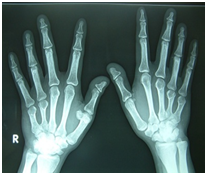

Figure 1-3 Short 4th and 5th fingers than normal person. Knuckle knuckle dimple dimple sign.

Figure 4 X ray hands: Short 4th and 5th metacarpals, large exostosis at distal end of 1st right metacarpals, both wrist normal.